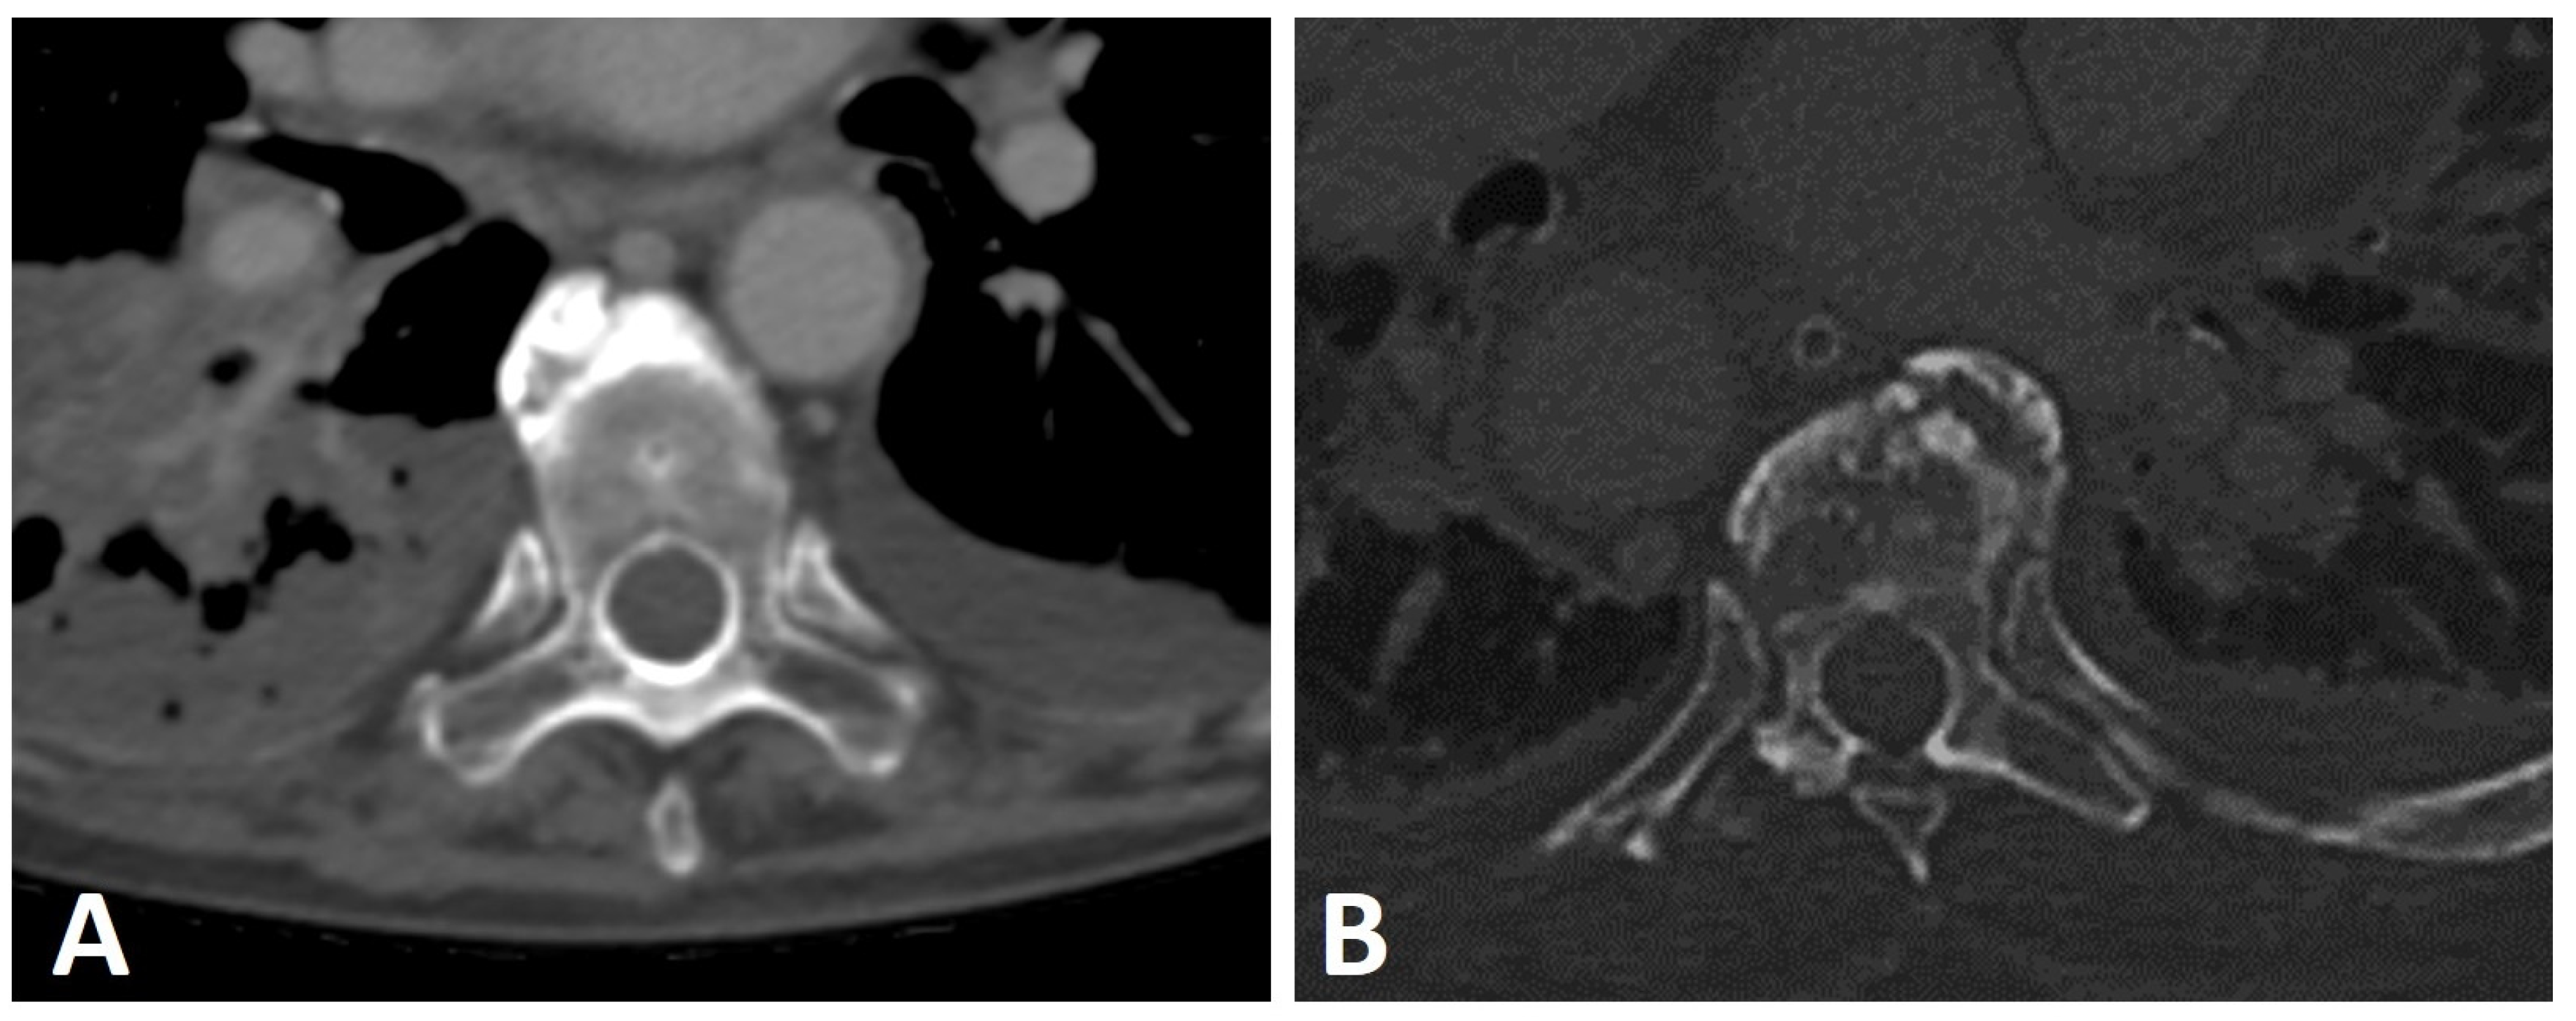

2.5. Sacroiliac Joints

To distinguish between SpA and DISH, the SIJs appear as an exclusion criterion in the Resnick and Niwayama criteria, so that findings compatible with sacroiliitis, such as erosions, sclerosis, and ankylosis of the SIJ on pelvic radiographs, preclude the diagnosis of DISH [1]. In subsequent studies, Resnick and co-workers described the presence of SIJ osteophytes, para-articular bony bridging, and coexisting osteoarthritis on pelvic radiographs of subjects with DISH [4,66]. Over time and with advances in imaging technology, the characterization of SIJ involvement in DISH has been refined for both CT and MRI. Extra-articular bridging osteophytes located ventrally to the SIJs, similar to flowing osteophytes in the spine, are commonly seen in DISH patients, resulting from enthesopathy of the involved ligament (Figure 7A) [67,68]. This anterior SIJ bridging overlying the SIJ on pelvic radiographs obliterates the joints, resulting in a false diagnosis of SIJ ankylosis, and thus SpA [67,69]. Indeed, studies evaluating the SIJs of subjects with DISH on CT have shown that anterior bridging of the SIJ is a common finding [70,71], but in contrast with the Resnick and Niwayama criteria, both intra-articular and posterior entheseal ankylosis are also prevalent in DISH (Figure 7B) [70,71].

Figure 7.

Axial CT images of the SIJs of two patients with DISH. (A) Characteristic extra-articular bridging osteophytes are seen anterior to the SIJs. (B) In addition to the ventral extra-articular osteophytes, clear ankylosis can be observed within the right and left SIJs.